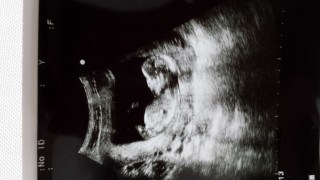

初めての経腹エコーで、6.7センチでした(^^)体をよじって元気に動いてました(^^)心音もしっかり聞こえて「うん、順調だねぇ!!」とのことでした☆

初ベビです♪

初めての妊娠で、今回の検診からお腹の上からのエコーになりました(^^) 前回まではキューピーちゃんだったのに、成長の早さにビックリです。 頭からお尻まで58.3mmでした。 検診中ずっと手足バタバタで可愛くてたまりませんでした(^^) エコー動画はDVDにしてもらってるので、今後も検診が楽しみ☆